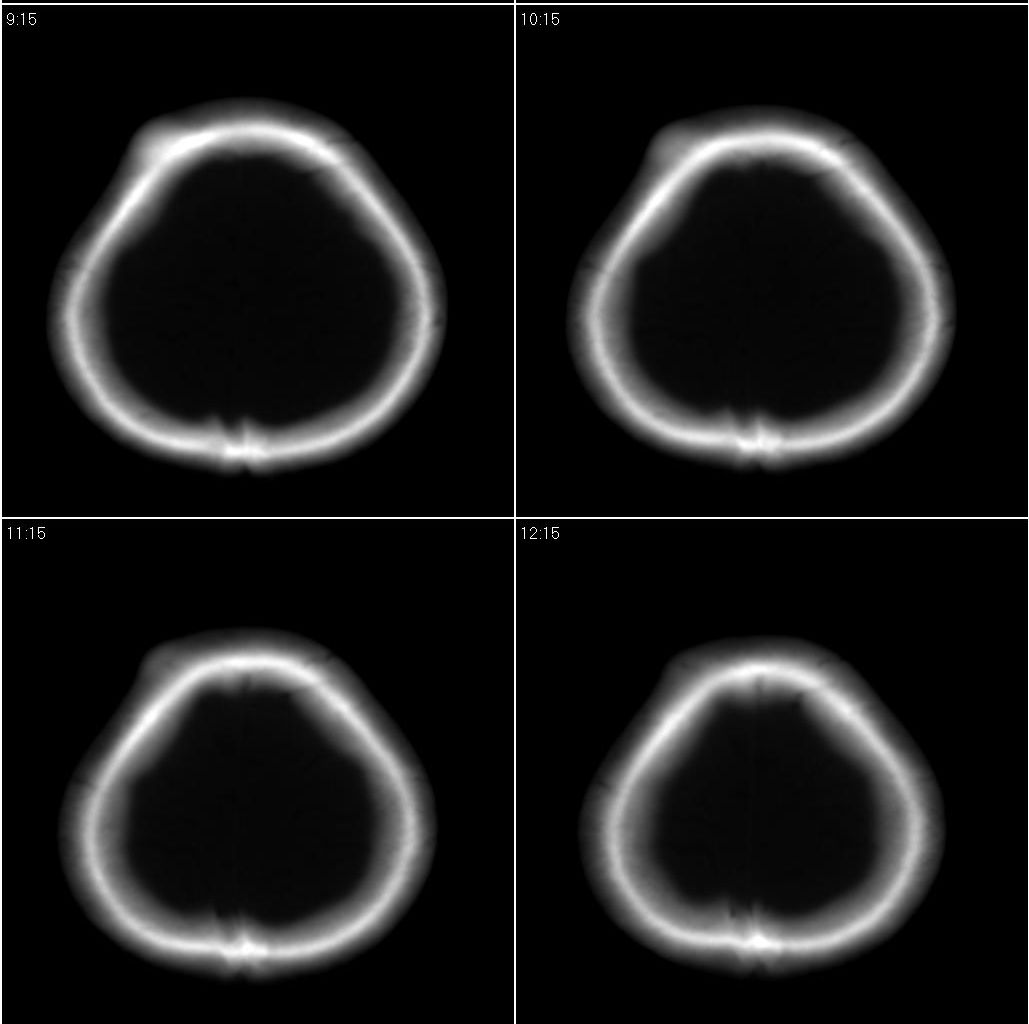

标题: CT16658:女性,49岁。发现右侧额部包块10余年。 [打印本页]

标题: CT16658:女性,49岁。发现右侧额部包块10余年。

应该选择骨窗,骨瘤=良性的经常就到。

骨瘤?建议上传骨窗!

右额部颅骨外板为主向外突出局限致密骨影,密度均匀,考虑额骨致密骨瘤

右侧额骨致密骨瘤。